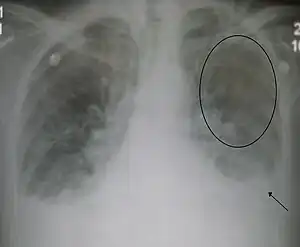

Acute interstitial pulmonary edema. Note enlarged heart size, apical vascular redistribution ( circle ), and small bilateral pleural effusions ( arrow ).